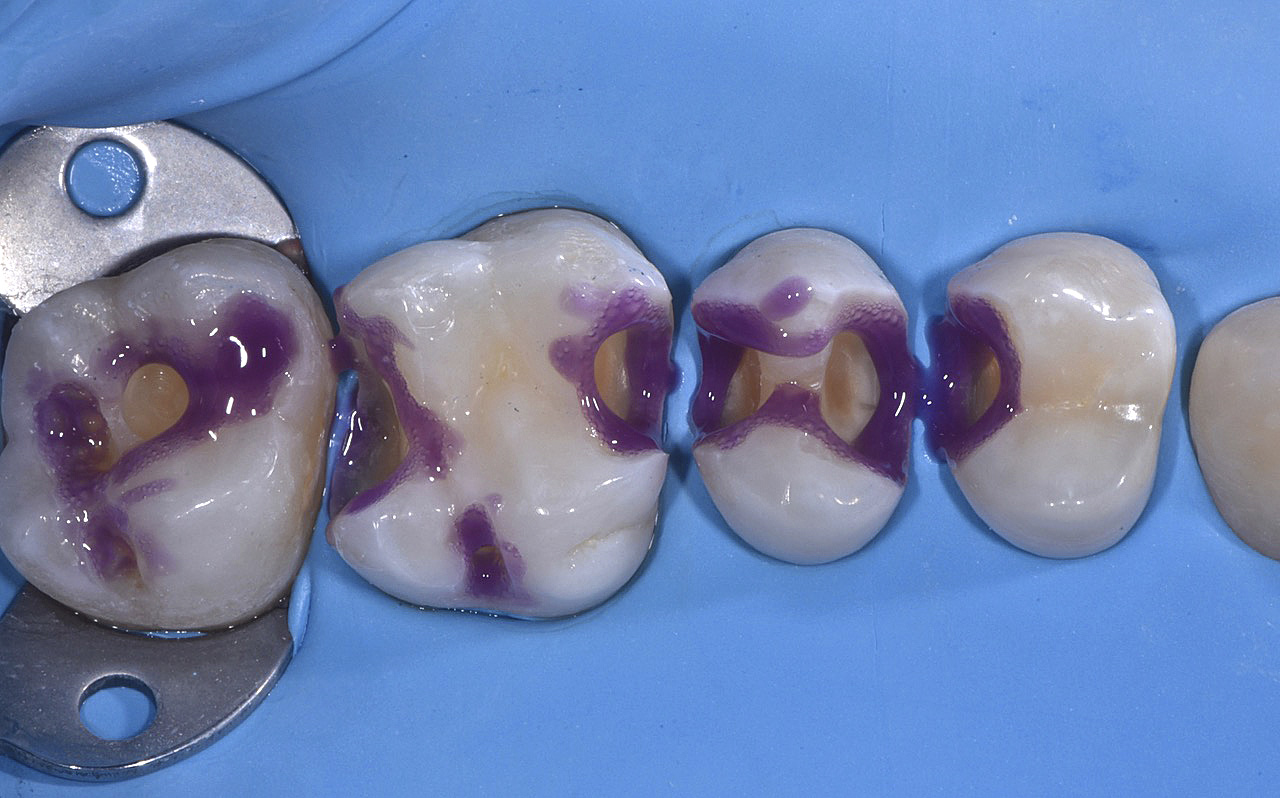

PREMESSA: in seguito all’estrazione dell’incisivo laterale superiore di destra, resasi necessaria per cause batteriche, si decide di affrontare il caso con il posizionamento di un impianto in sostituzione dell’elemento mancante dopo guarigione del sito infetto. Con tecniche rigenerative sia dei tessuti ossei mancanti a causa dell’infezione pregressa, sia dei tessuti gengivali che appaiono inizialmente troppo spostati in alto, si ripristina una corretta morfologia delle parabole (contorni) gengivali e delle papille interdentali (triangoli di gengiva tra due denti vicini).